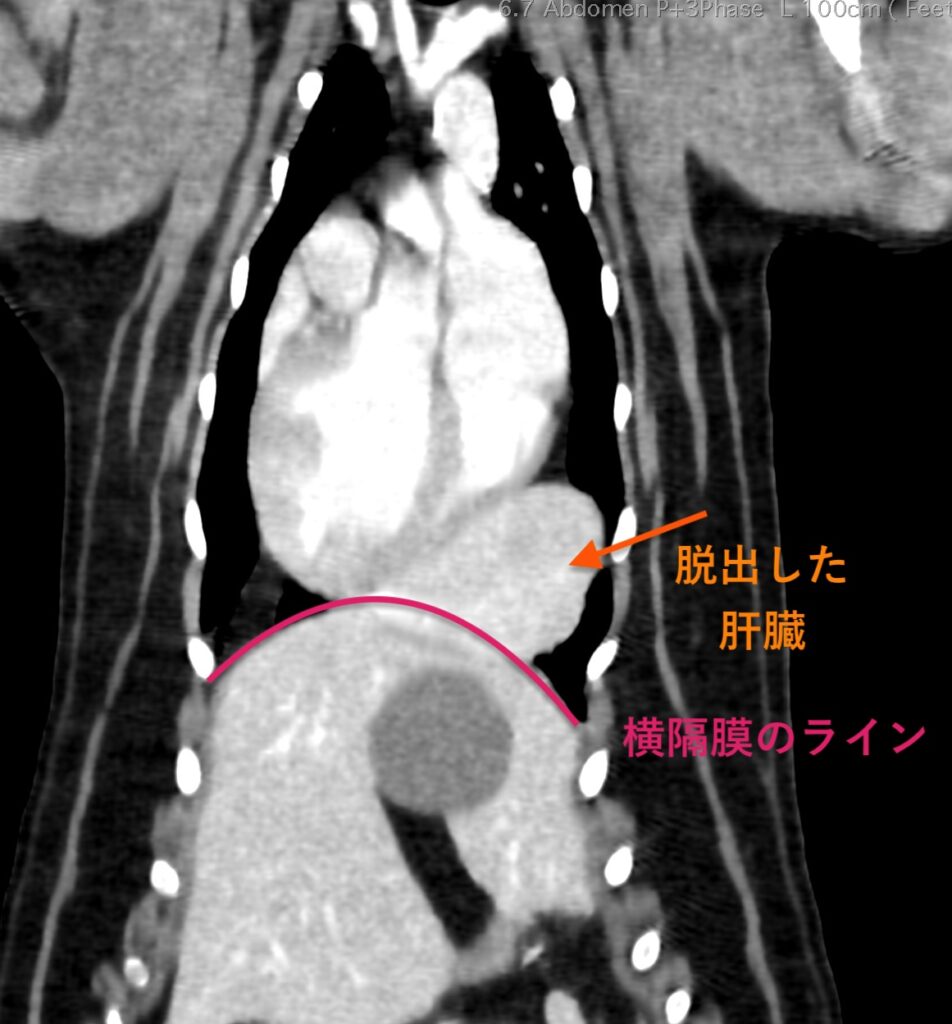

エコー検査、CT検査にて胸腔内(心臓尾側)に肝臓実質(方形葉)が脱出。

・心膜横隔膜ヘルニア